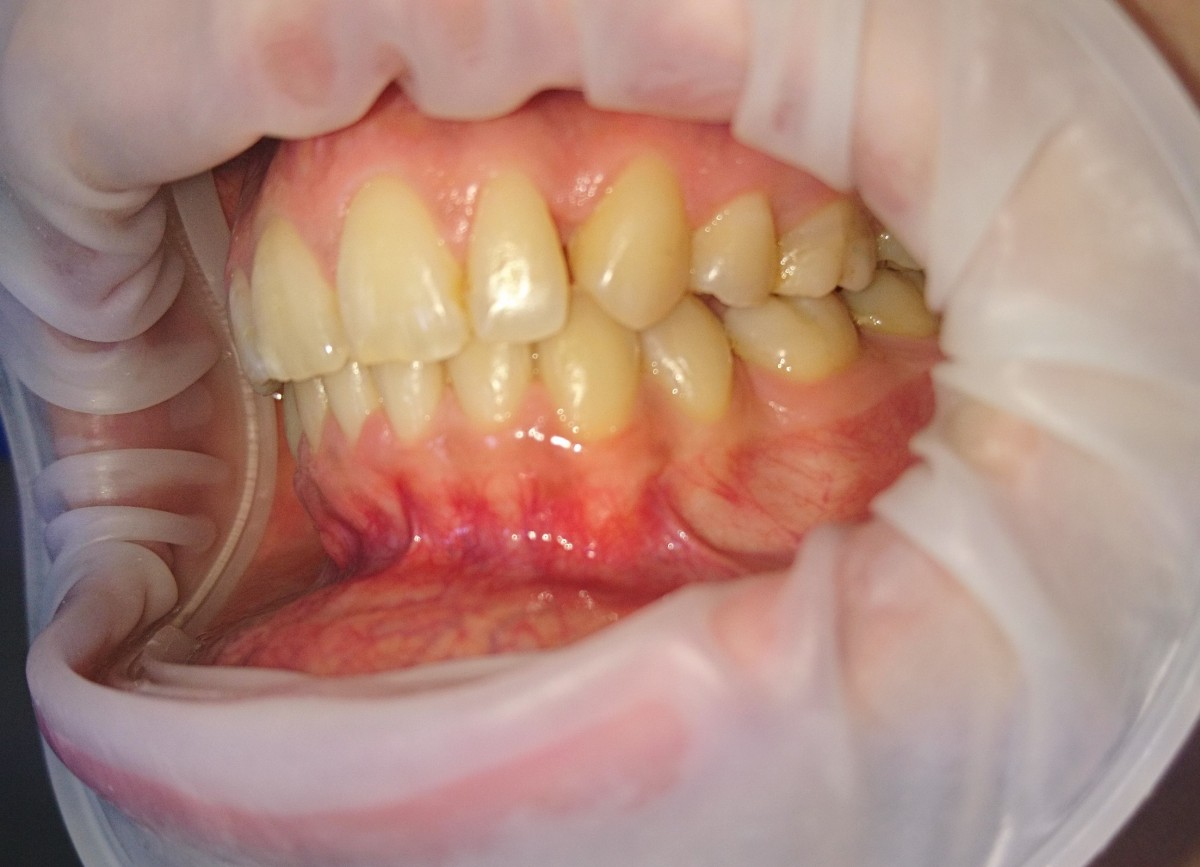

Pacient 23 ani. Extracție 1.4, 2.4, 3.5, 4.5, aparat ortodontic fix ceramic.